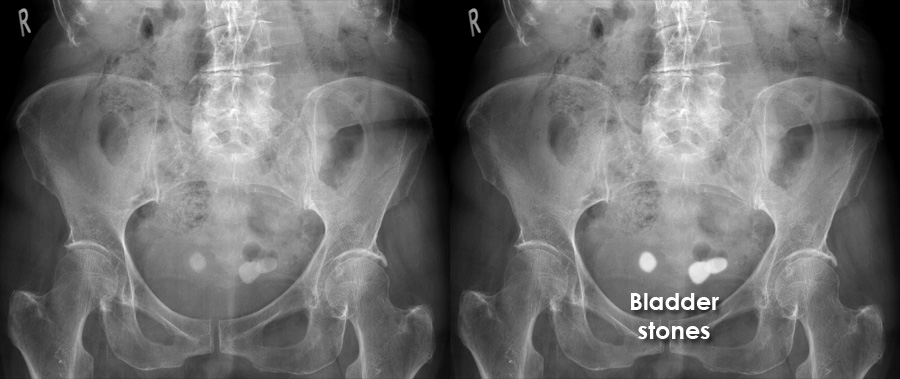

Abdominal X ray Gallery Calcification Bladder Stones

Abdominal X ray Gallery Calcification Bladder Stones